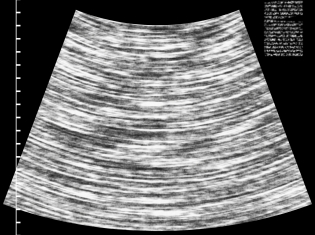

An ultrasound uses sound pressure to see inside a patient. Unlike a CT scan, it doesn’t use radiation.

When diagnosing kidney stones, doctors most often use CT scans. That method uses X-rays to create a cross-section image of a patient.